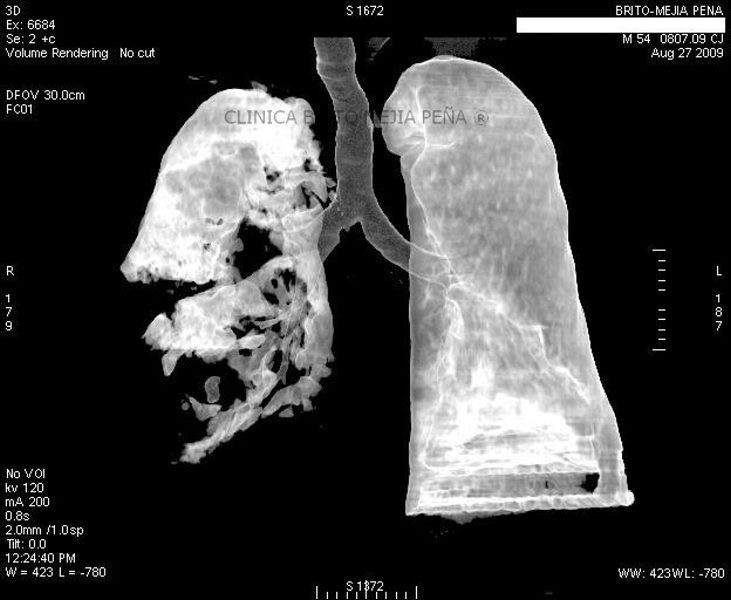

Trombosis arteria pulmonar 3D aire